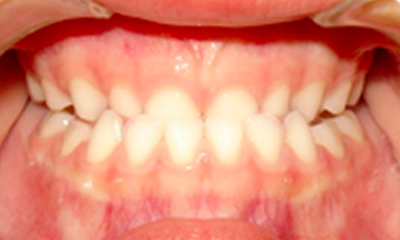

Mordida cruzada posterior

As mordidas cruzadas posteriores são alterações transversais dos arcos dentários e não se autocorrigem.

Caso 1

As imagens abaixo ilustram um caso de mordida cruzada posterior. Como se pode notar pelas imagens abaixo, a mordida cruzada posterior - quadrante direito do arco maxilar - foi corrigida com a ortodontia interceptativa.